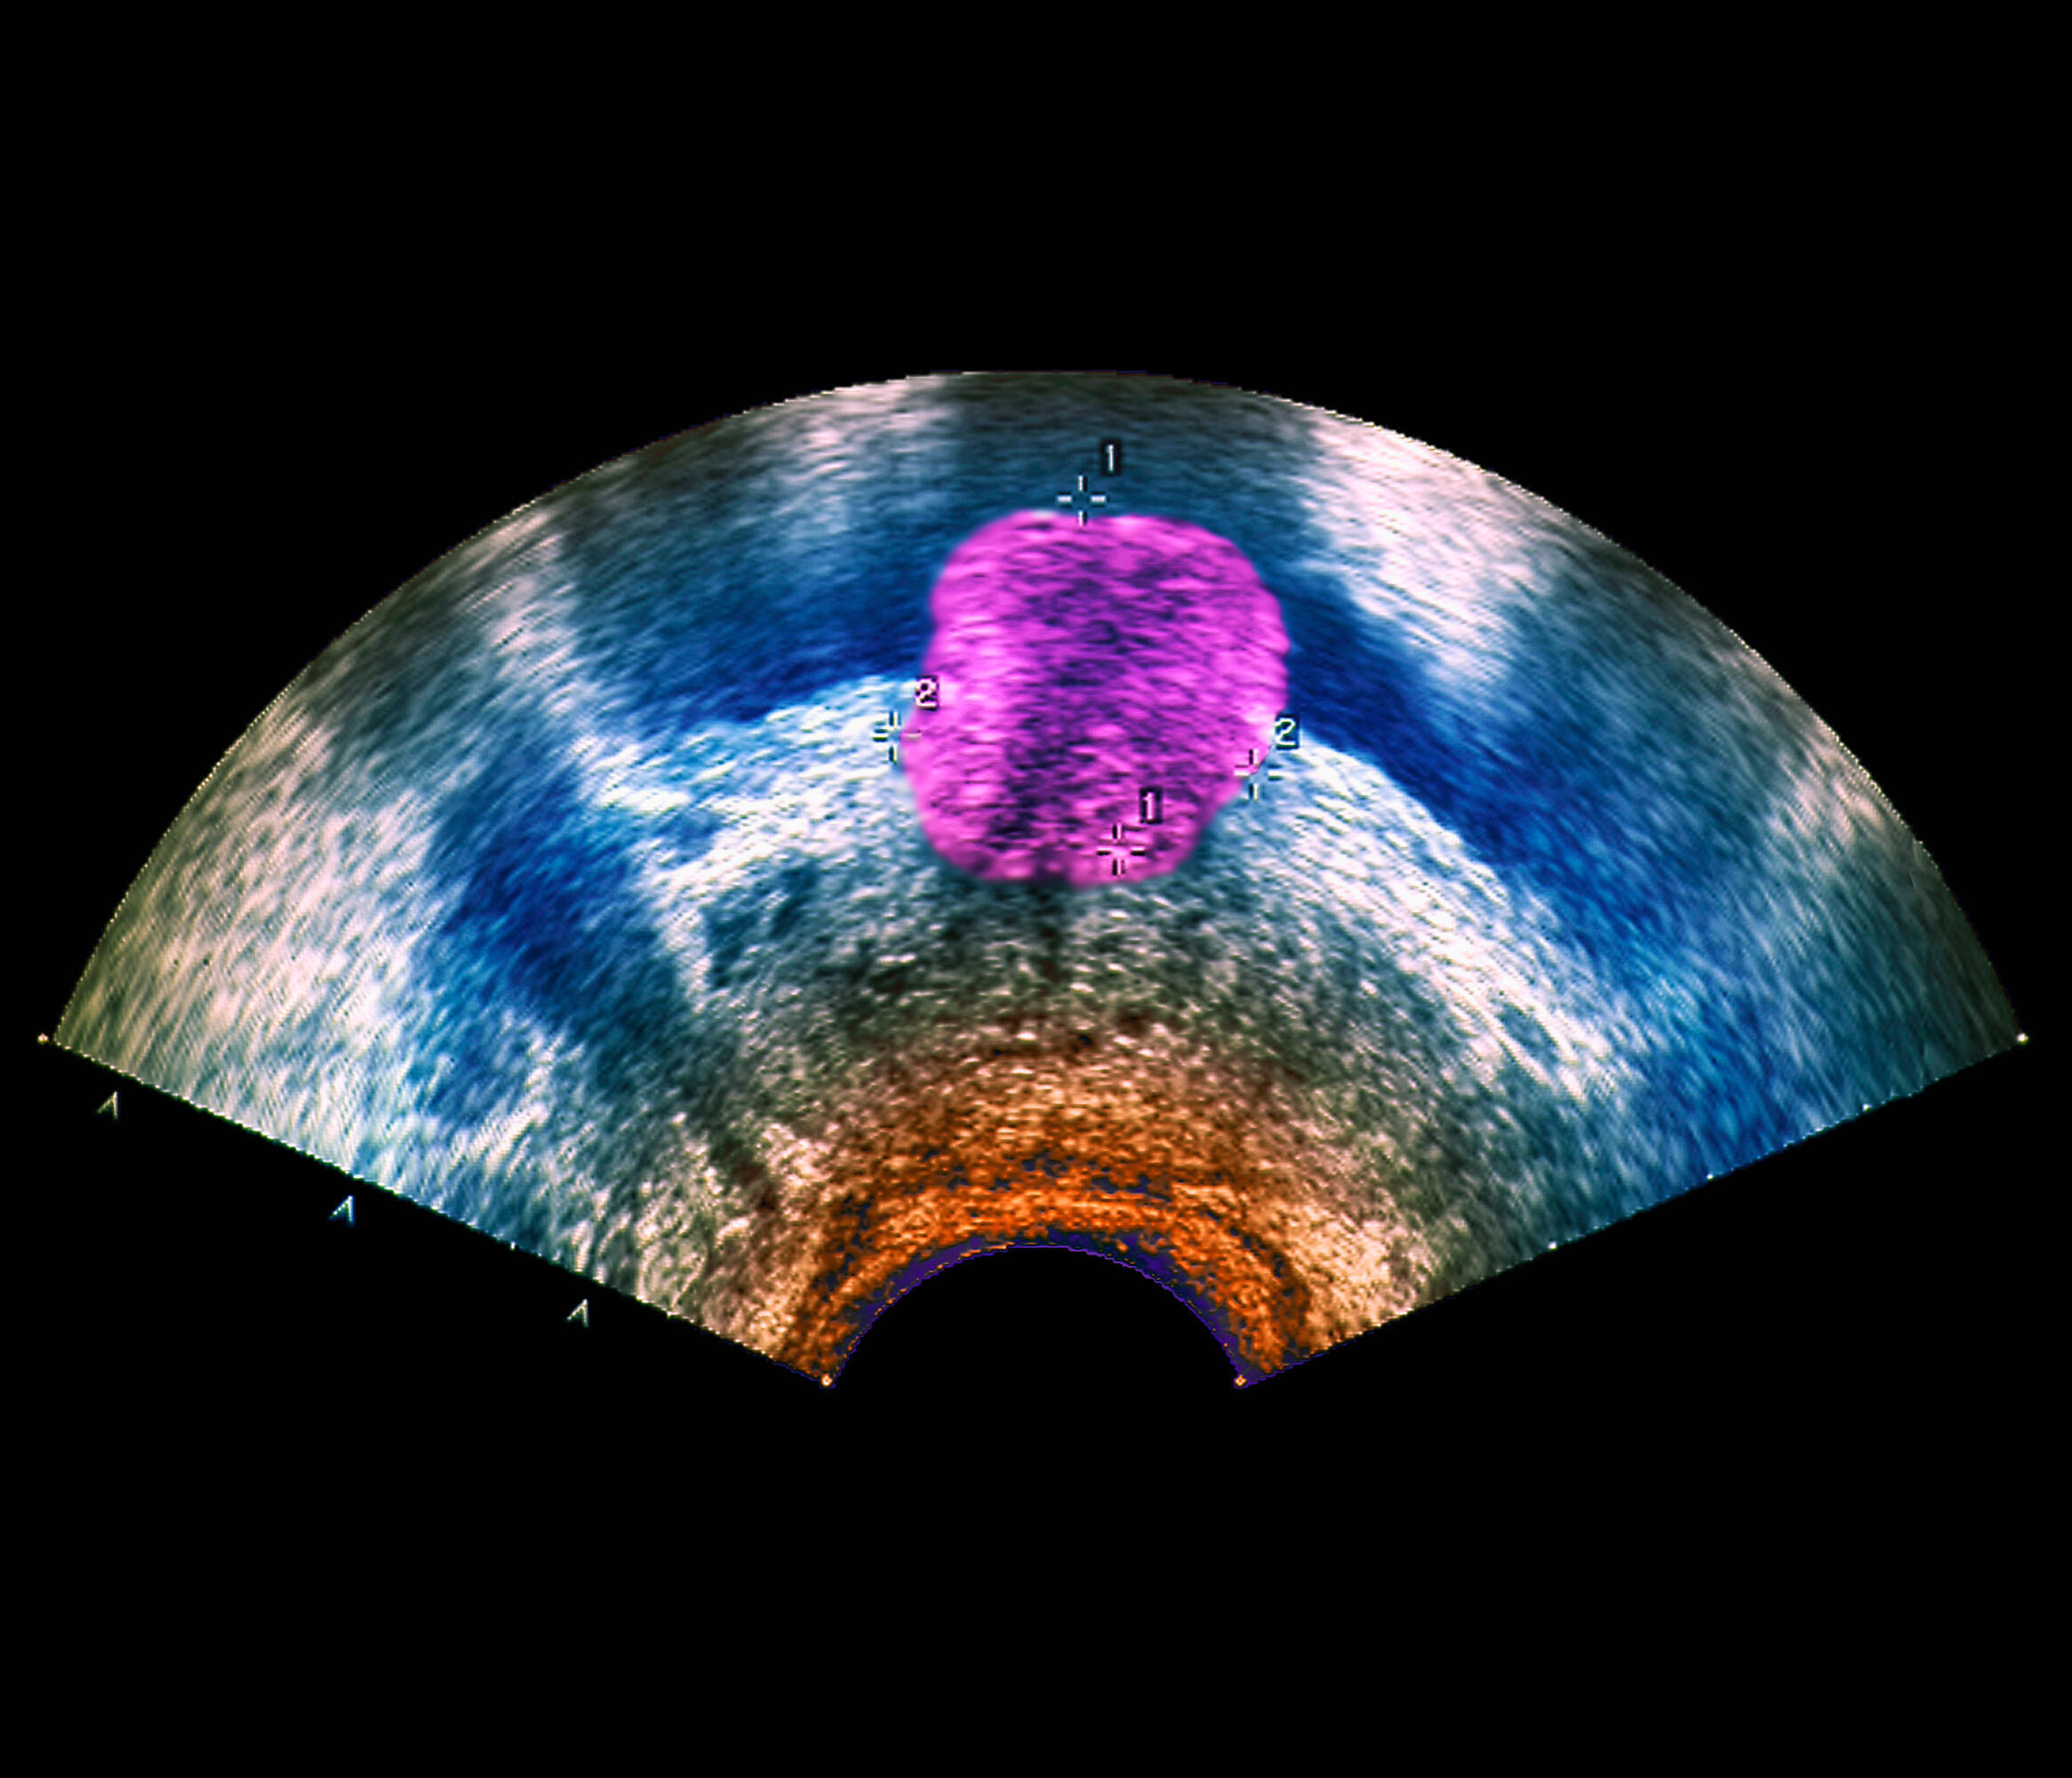

- Cancerul de prostată non-metastatic rezistent la castrare (nmCRPC), în special pentru pacienții cu risc crescut de a dezvolta metastaze;

- Cancerul de prostată metastatic sensibil la terapia hormonală (mHSPC).

Datele statistice arată că aproximativ unul din trei pacienți diagnosticați cu mHSPC (cancer de prostată metastatic sensibil la terapia hormonală) supraviețuiește cel puțin cinci ani, însă majoritatea acestora evoluează spre forma rezistentă la castrare (CRPC).

Chiar dacă majoritatea bărbaților sunt diagnosticați inițial cu o formă localizată, 3,4 abordabilă prin chirurgie curativă sau radioterapie, riscul de recidivă și metastază rămâne semnificativ. În aceste stadii, terapia de deprivare androgenică (ADT) constituie pilonul principal de tratament, alături de opțiuni precum inhibitorii căii receptorilor androgenici sau chimioterapia cu docetaxel. Cu toate acestea, progresia către stadii metastatice avansate rămâne o provocare majoră, fiind asociată cu o morbiditate ridicată și o supraviețuire limitată.

În acest context, detectarea timpurie a cancerului de prostată rămâne condiția esențială pentru creșterea ratelor de supraviețuire. Implementarea screeningului regulat și o mai bună cunoaștere a factorilor de risc sunt pilonii care permit identificarea bolii în stadii curabile, înainte ca aceasta să progreseze către forme severe, dificil de controlat.